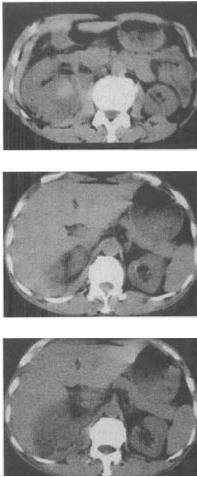

男,25岁,右腰部疼痛伴血尿,有外伤史,CT扫描如图所示,应诊断为()。

A、右肾挫伤并包膜下血肿

B、右肾血管平滑肌脂肪瘤

C、右肾癌

D、右肾梗死

E、右肾脓肿

A